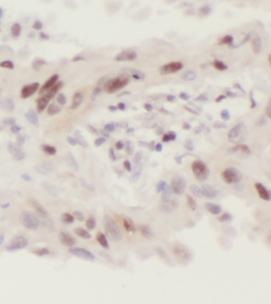

| 验证图片 | Immunohistochemistry of paraffin-embedded human lung cancer using FNab01809(CNOT4 antibody) at dilution of 1:50 mouse skeletal muscle tissue were subjected to SDS PAGE followed by western blot with FNab01809(CNOT4 antibody) at dilution of 1:500 |